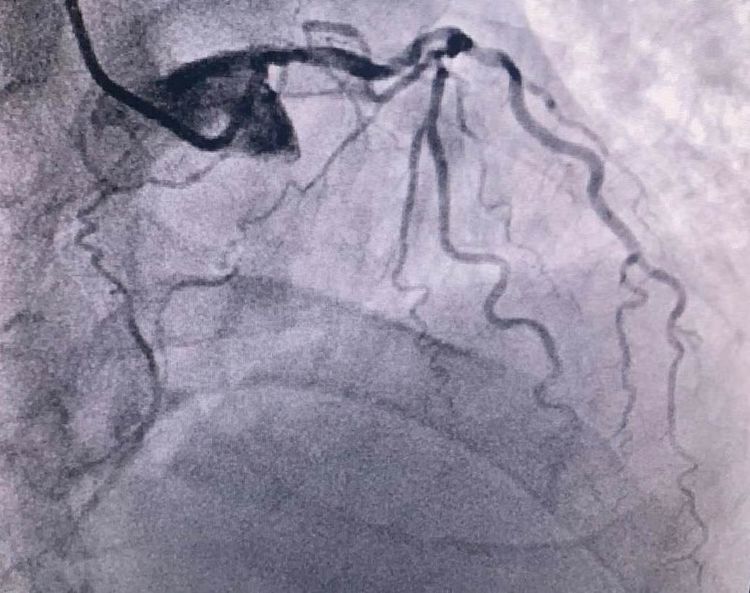

患者前降支、右冠100%閉塞,LCX中段60%狹窄。命懸一線,手術(shù)臺(tái)上持續(xù)胸痛。和患者家屬及時(shí)溝通后,決定行PTCA術(shù)。血壓低至60/40mmHg,在主動(dòng)脈內(nèi)球囊反博的支持下緊急行PCI術(shù)。軌道很快建立,導(dǎo)絲也及時(shí)通過(guò)病變血管,噩夢(mèng)來(lái)了,患者發(fā)生室顫了。在吳棟梁院長(zhǎng)的指揮下,李陽(yáng)主任和心臟團(tuán)隊(duì)的成員共同努力下,除顫、冠脈內(nèi)溶栓、多個(gè)球囊輪流上陣,患者病情平穩(wěn)了,罪犯血管及時(shí)開(kāi)通,血流恢復(fù)三級(jí)血流。平安下臺(tái),準(zhǔn)備擇日再處理冠脈情況。